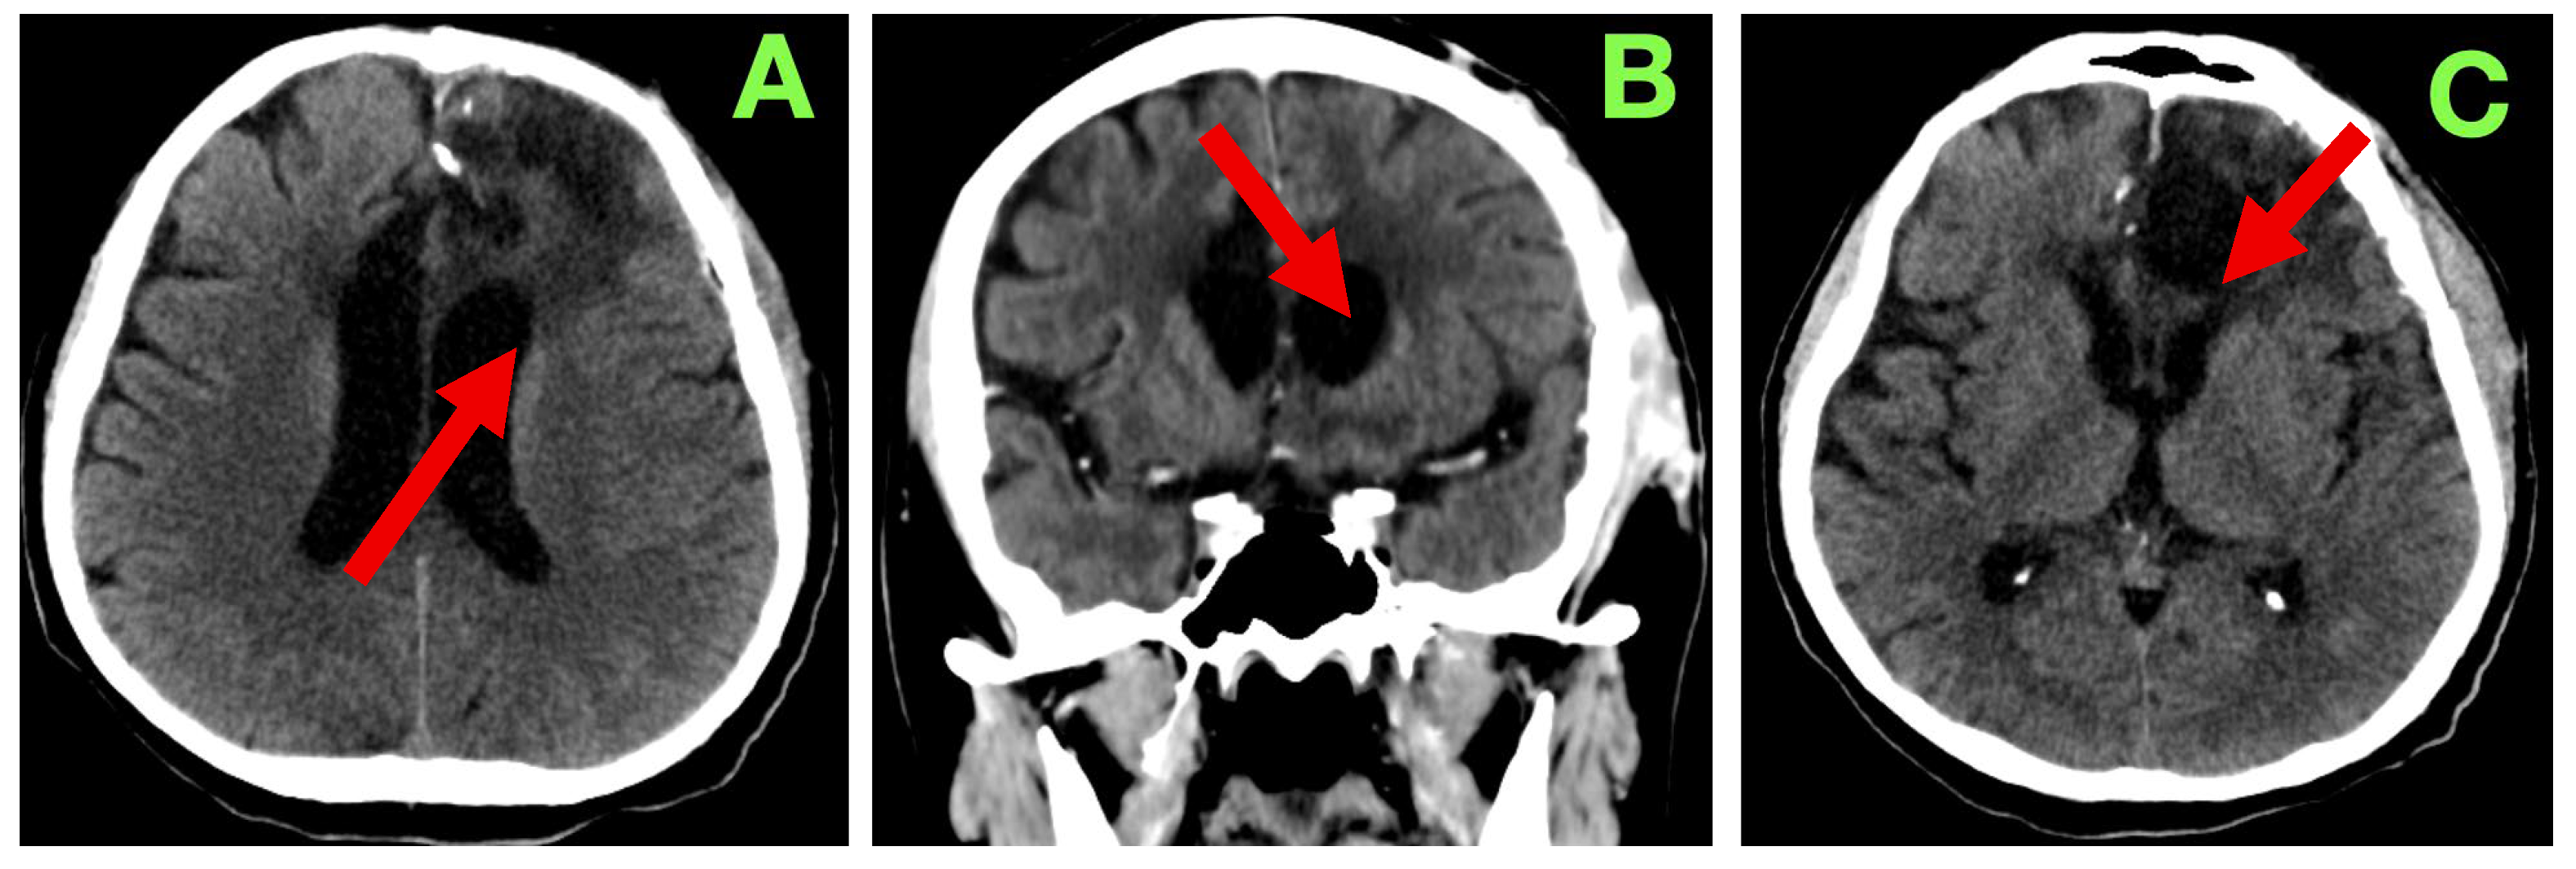

On examination, the strength of motor function was intact bilaterally with no noticeable asymmetries or fasciculations or evident fatigability in the exam. The deep tendon reflexes were symmetric and there were flexor responses on the Planta response testing. Gait and coordination were normal on testing. On language examination, the patient showed fluent expressive output with mild anomia, but observed accuracy with respect to syntax, repetition, and reading comprehension. On cognitive assessment there was intact short-term memory, attention span, and executive function testing. As part of standard follow-up, a non-contrast cranial CT (Figure 3) was completed at 3 months. This scan showed a stable post-operative cavity without any new enhancement in the cavity or hemorrhagic complication or indication of any new hydrocephalus. There was also considerable reduction in perilesional edema. The ventricular appearance had returned to their apparent normal appearance, with no evident midline shift/sub-dural collection/sub-acute delayed infarct. Relative to the original report, they interpreted the findings as consistent with radiological stability of the surgical site and that there continued no progression, particularly with the absence of any new findings.

Figure 3. Three-month post-operative cranial CT scan. (A): Axial section demonstrating a well-defined left frontal resection cavity (red arrow) with smooth margins and no residual mass effect. Compared to the immediate post-operative stage, most of the surrounding vasogenic edema has resolved. Ventricular configuration is symmetric, with no midline shift or hydrocephalus. (B): Coronal reconstruction confirming stability of the resection cavity (red arrow), with no evidence of recurrent mass lesion. Cortical–subcortical architecture around the margins remains preserved, and no abnormal extracerebral collections are present. (C): Caudal axial slice showing the inferior aspect of the resection cavity (red arrow), with basal ganglia and thalamic anatomy intact. No delayed ischemia, hemorrhage, or secondary injury is observed, and the overall appearance is consistent with post-operative stability at three months.